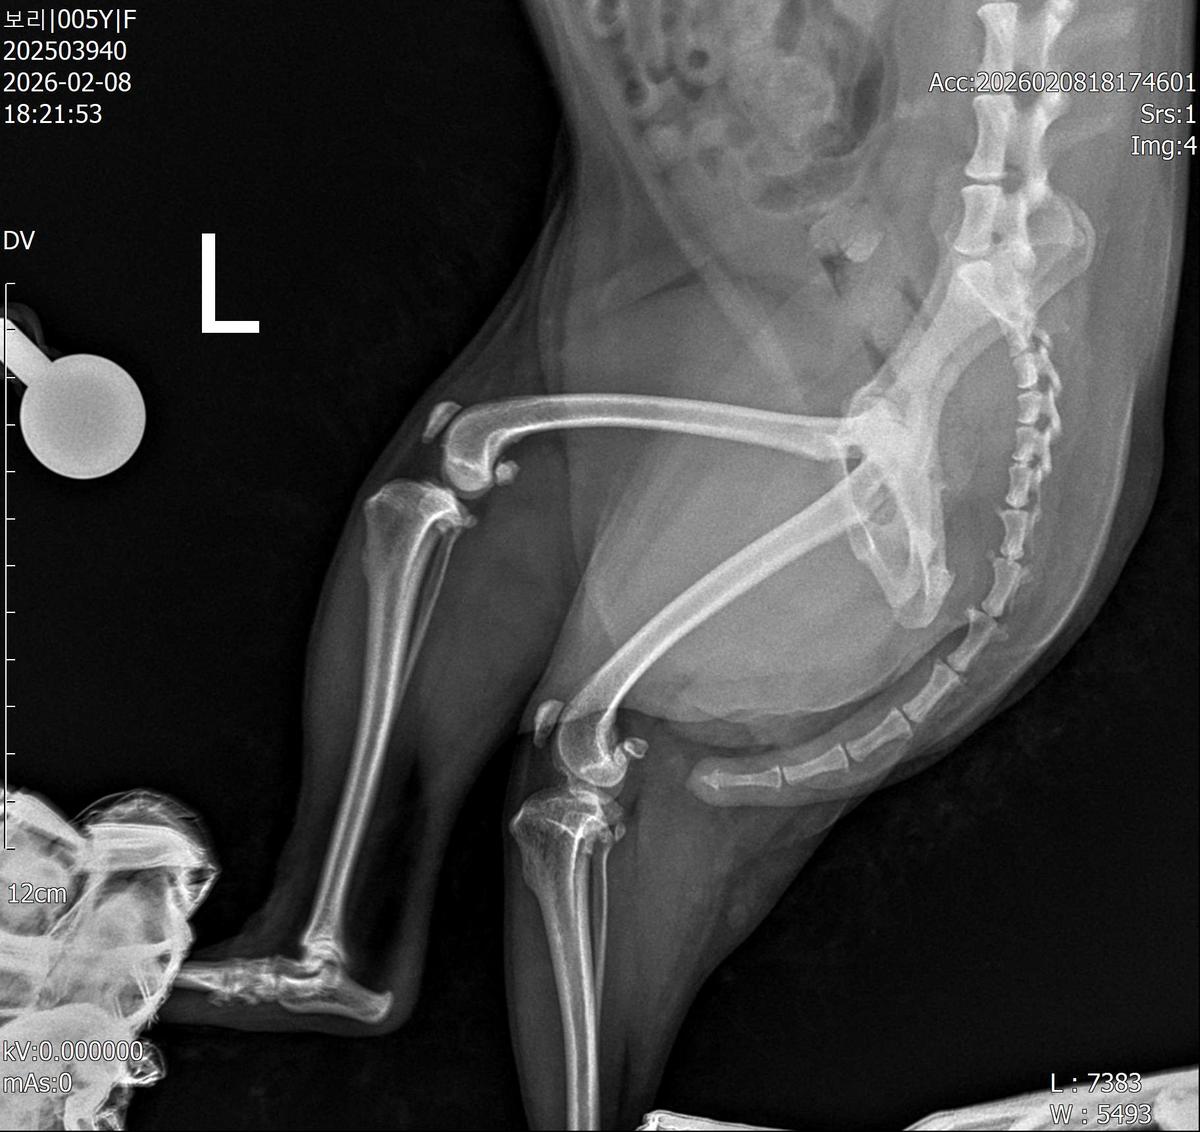

강아지 슬개골탈구 진단 받았습니다 몇군데 병원을 다녀봤는데 진단이 달라 궁금해서 질문 해봅니다 일단 저희 강아지는 오른쪽 다리를 갑자기 들고 다니고 절어 병원을 방문하게 되었고요 왼쪽은 증상이 없지만 오른쪽만 있는 상태였습니다 첫번째랑 두번째 병원에서는 슬개골 탈구 진행중이고 왼쪽이 3기 오른쪽이 2기 정도라고 했습니다 하지만 왼쪽은 아예 빠져있어 증상도 없고 아파하지도 않는다고 했고 오른쪽은 빠졌다 안빠졌다 해서 증상이 있다고 했고 십자인대가 파열된 걸론 보이지 않는다고 했습니다 그래서 양쪽 슬개골탈구 수술만 진행하면 된다고 했고요 근데 세번째 병원에서는 둘다 왼쪽이 좀 더 심한 슬개골 탈구 3기 정도라고 했고 오른쪽만 십자인대 부분파열이 보인다고 했습니다 그래서 십자인대 파열이 아닌 왼쪽은 굳이 수술할 필요가 없고 나중에 십자인대 파열이 오거나 증상이 나타나면 그때 수술하면 된다고 했습니다 그래서 오른쪽 슬개골탈구 수술과 tplo를 하는 방식으로 수술을 한다고 했습니다 여기서 궁금한점은 1. 십자인대 파열이 사진상으론 보이지 않는다고 하는데 사진상으로 알 수 있는 건가요? 2. 십자인대 파열이 아니면 슬개골탈구 수술을 굳이 할 필요 없다고 하셨는데 맞는 건가요? 3. 꼭 슬개골탈구와 십자인대 수술을 같이 해야 결과과 더 좋아지나요? 4. 사진상으로 십자인대와 슬개골 수술을 같이 해야할까요? 5. tplo 수술방법이 가장 안전하고 좋은 수술방법인가요? 6. 슬개골탈구로 인해 십자인대가 끊어지는건 아니라고 들었는데 맞나요? 슬개골 탈구 수술로 십자인대를 예방할 수 있나요?